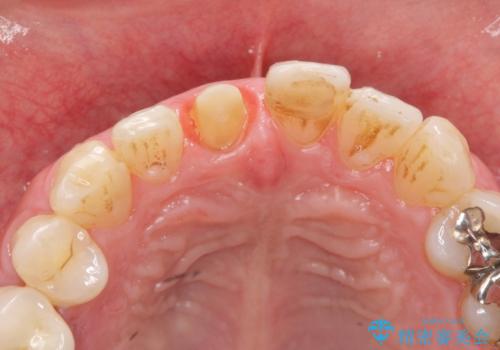

前歯の変色を改善 オールセラミック治療

- 目立つ前歯の変色の改善を希望され来院されました。

根管治療を行いそのままにしていると歯は、徐々に変色を来します。

感染の疑われる根管内に対し再度根管治療を行い、セラミッククラウンを作製することで審美性の回復します。